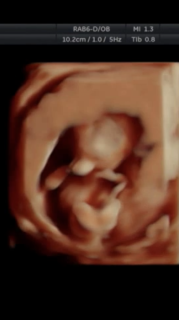

初めての3Dエコー。 89㎜14w4d相当でした。 しっかり映っててびっくり! 指しゃぶりしててかわいい連呼(笑) もうすでに親バカ発揮です(笑) 早く抱っこしたいな(^^) 元気に育ってくれてて日々感謝